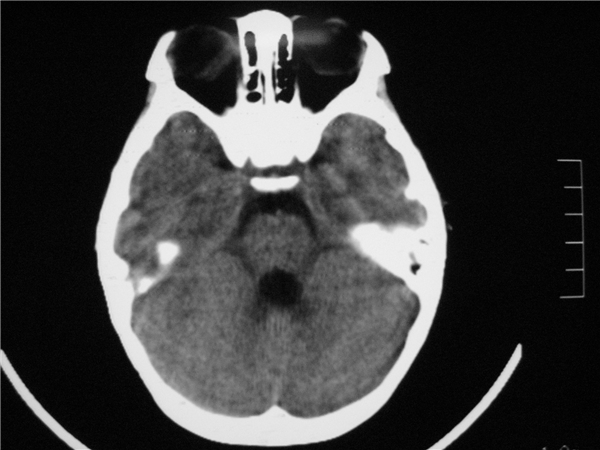

标题: PED2843: CT-23675 F 4Y 大家看看颅内有问题没。 [打印本页]

标题: PED2843: CT-23675 F 4Y 大家看看颅内有问题没。

四脑室扩大,三脑室稍扩大上移

胼胝体发育不全??

四脑室扩大,,六脑室

四脑室扩大,密度降低,图像的问题?建议mr扫描。